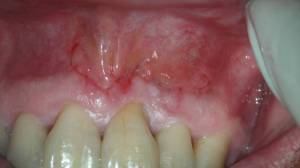

Después de un mes, le volvimos a citar: